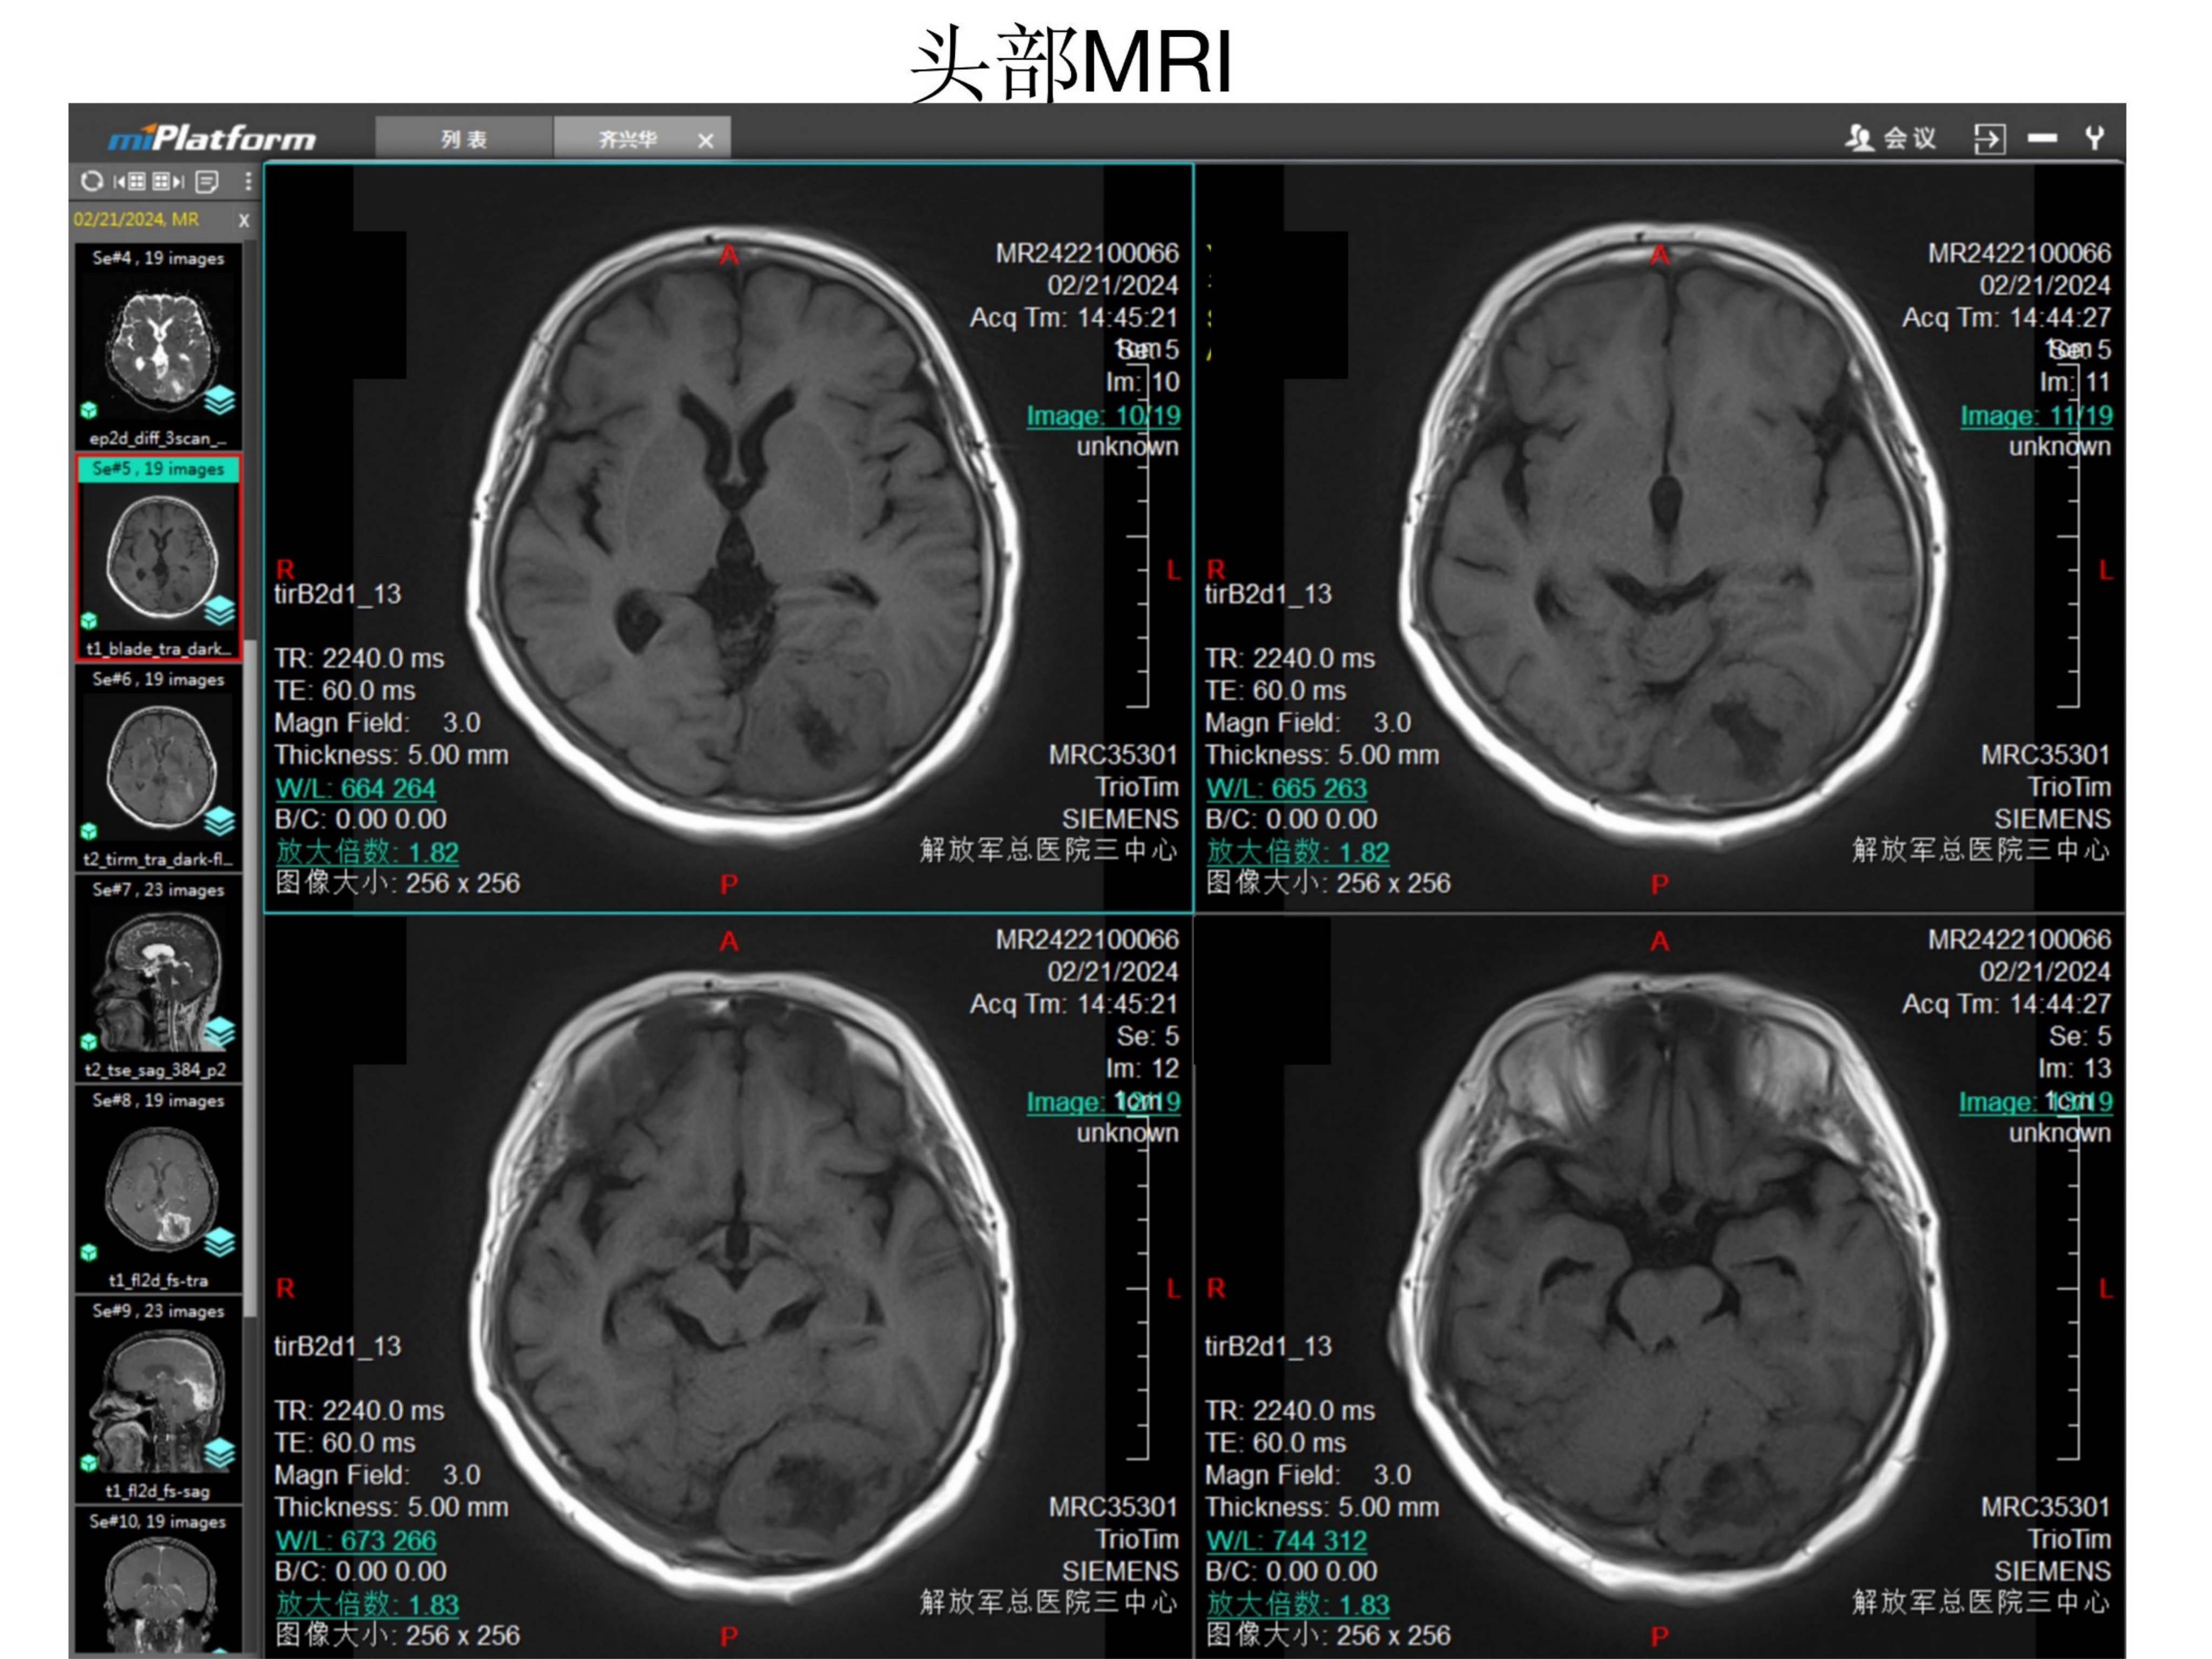

等T1信号

增强后可见肿瘤穿透小脑幕,幕上下均有肿瘤

肿瘤并未穿过大脑镰到对侧,SSS后1/3通畅。

肿瘤并未穿过大脑镰到对侧,SSS后1/3通畅。周边脑组织水肿不明显明显。证明蛛网膜界面尚完整。